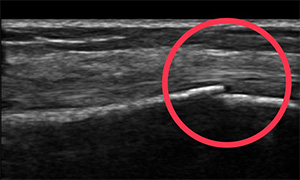

ケガ・スポ-ツ障害はエコ-でチェック!!

エコ-(超音波画像診断装置)

問診・触診を行いエコ-でケガの状態を確認して施術や固定(テ-ピングなど)をします。

実例①

4歳児、車のドアに指を挟まれケガをする。骨にキズの疑いがある為提携先の整形外科に紹介しました。